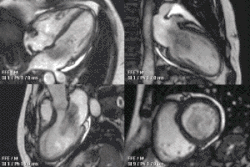

Heart function using cine imaging

Functional and structural information is acquired using bSSFP cine sequences. These are usually retrospectively-gated and have intrinsically high contrast in cardiac imaging due to the relatively high T2:T1 ratio of blood compared to myocardium. Images are typically planned sequentially to achieve the standard cardiac planes used for assessment. Turbulent flow causes dephasing and signal loss allowing valvular disease to be qualitatively appreciated. The left ventricular short axis cines are acquired from base to apex and are used for quantifying end-diastolic and end-systolic volumes, as well as myocardial mass. Tagging sequences excite a grid pattern that deforms with cardiac contraction allowing strain to be assessed.

Example CMR images. In sequence: a coronal localiser, 2 chamber cine, 4 chamber cine, left ventricular short axis cine, and tagged image. Additional cines of the left ventricular outflow tract and aortic valve may also be acquired.